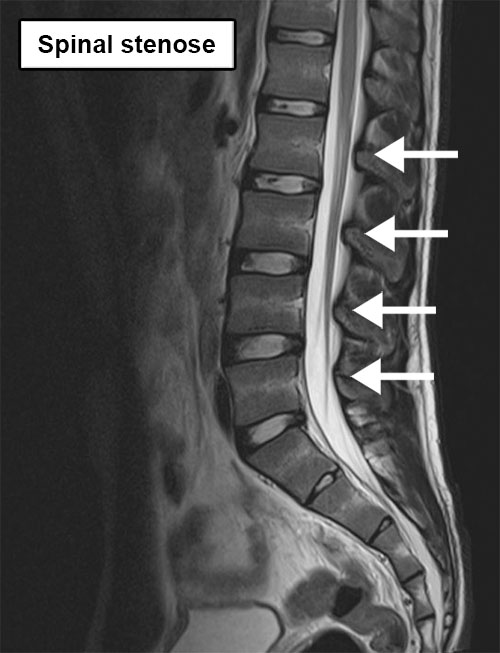

Ved spinal stenose er ryggmargskanalen innsnevret. Dette kan føre til at én eller flere nerverøtter kommer i klem. De komprimerte nervene kan føre til smerter i bena ved gange. Dette er også kjent som nevrogen claudicatio.

Den lumbale ryggsøylen består av virvlene i korsryggen. Virvlene er stablet oppå hverandre og danner en lang, vertikal kanal i midten. Gjennom denne kanalen går en stor bunt med nerver. Ved stenose i den lumbale ryggsøylen er ryggmargskanalen innsnevret. Dette kan føre til at nerverøttene i kanalen kommer i klem. Dette gir symptomer i det området nerven forsyner.

Diagnosen stilles på bakgrunn av en samtale om symptomene i kombinasjon med en fysikalsk undersøkelse. Røntgenbilder, CT-scan eller MR kan være nyttige for å vise innsnevringen og for å bestemme den eksakte plasseringen.